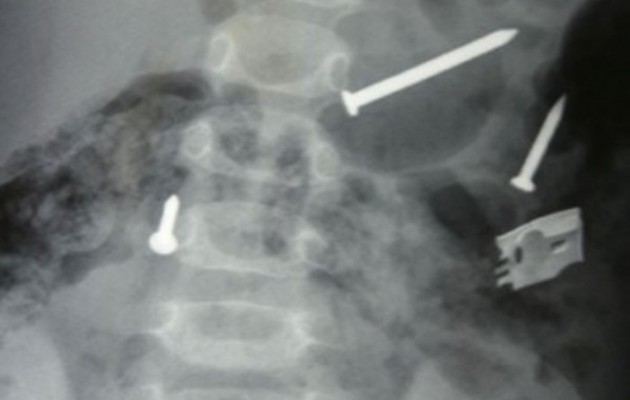

Δεν πίστευαν στα μάτια τους οι γιατροί στο Πανεπιστημιακό Νοσοκομείο Ρίου, όταν είδαν τις ακτινογραφίες ενός ασθενούς, ο οποίος είχε μετατρέψει το στομάχι του σε… θυρίδα ασφαλείας, καταπίνοντας διάφορα πολύτιμα αντικείμενα.

Οι γιατροί είδαν στην ακτινογραφία να διαγράφονται, ένα ρολόι, κάποια δαχτυλίδια, ένα κομπολόι, ένα σταυρουδάκι με αλυσιδίτσα, ενώ υπάρχουν ακόμα καρφίτσες, κέρματα, βίδες, μεταλλικά παξιμάδια και πολλά άλλα αντικείμενα.

Επειδή όλα αυτά εγκυμονούσαν μεγάλο κίνδυνο για την υγεία του ασθενούς, αποφασίστηκε να γίνει άμεσα επέμβαση ώστε να αφαιρεθούν όλα. Με τη βοήθεια της σύγχρονης τεχνολογίας κατάφεραν να απομακρύνουν από το «εσωτερικό» του ασθενούς, όλα αυτά που φαίνονταν στην ακτινογραφία.

Σύμφωνα με πληροφορίες οι γιατροί συγκέντρωσαν περίπου 24 αντικείμενα.